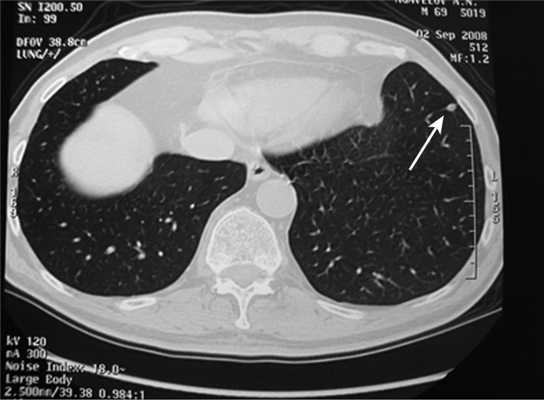

Все больные были разделены на группы в зависимости от размера очагового образования: 1-ю группу (диаметр ООЛ 0,5-1; рис. 1) составили 9 мужчин и 14 женщин, 2-ю группу (диаметр ООЛ 1-2 см; рис. 2) - 30 мужчин и 13 женщин, 3-ю группу (множественные ООЛ; рис. 3) - 27 мужчин и 17 женщин.

Рис. 1. Компьютерная томограмма груди пациента 1-й группы